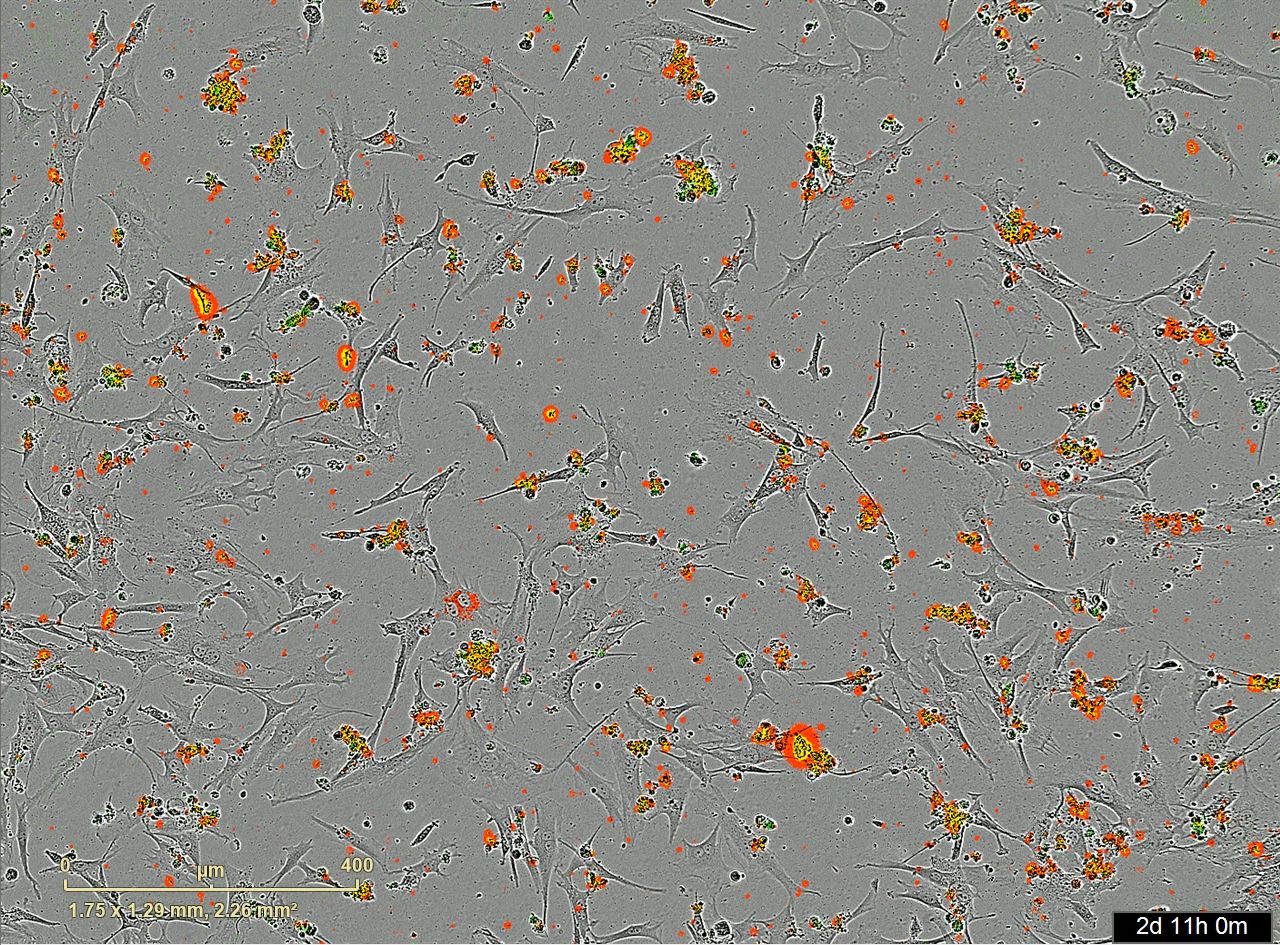

Dem COVID-19-Impfstoff aus der Humangenomik einen Schritt näher gekommen: ‚Aufregend!‘